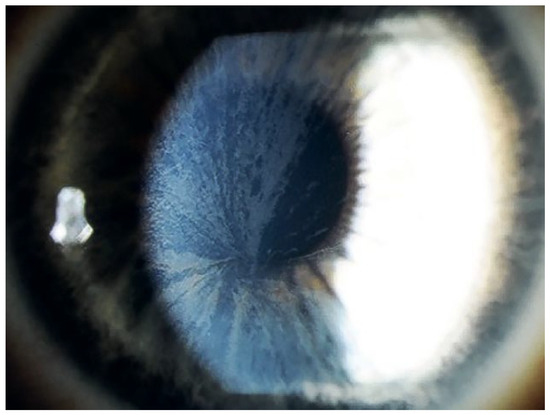

Fabry disease – a rare but important cause of left ventricular hypertrophy. Fabry disease (synonym: Morbus Fabry, Anderson Fabry disease) is an Xlinked lysosomal storage disease due to a deficient activity of alpha-galactosidase A. This leads to pathological glycosphingolipid metabolism, resulting in deposition [...] Read more.

Fabry disease – a rare but important cause of left ventricular hypertrophy. Fabry disease (synonym: Morbus Fabry, Anderson Fabry disease) is an Xlinked lysosomal storage disease due to a deficient activity of alpha-galactosidase A. This leads to pathological glycosphingolipid metabolism, resulting in deposition of glycosphingolipids in lysosomes and body fluids. There is evidence that the glycolipids also accumulate extralysosomally, which is a very important factor in the pathogenic impact. Cardiac involvement is one of the most important disease manifestations because the patients mainly die from cardiac complications. There are two phenotypes: classic and later-onset. First symptoms of the classic phenotype occur during the childhood and include angiokeratomas, hypohidrosis, cornea verticillata, and tortuosity of conjunctival and retinal vessels. Young patients typically suffer from acroparaesthesias, abdominal cramping and pain crises. With advancing age, the progressive sphingolipid deposition, particularly in the endothelial cells, cardiomyocytes and podocytes, leads to arterial hypertension, cardiomyopathy, nephropathy and premature strokes. In contrast to the classic phenotype, patients with the later-onset phenotype lack the early disease symptoms. They typically present to the hospital in adulthood with cardiomyopathy or with nephropathy. In females, alpha-galactosidase A activity can range from low to normal owing to random X-chromosome inactivation. Generally, females have a milder phenotype because of the second, unaffected X-chromosome. Patients with Fabry cardiomyopathy suffer from left ventricular hypertrophy, conduction abnormalities and valvular involvement, as well as from diastolic and/or systolic heart failure symptoms. The enzyme activity determination in leucocytes is diagnostic in males but can be misleading in females owing to random X-chromosome deactivation. Thus, genetic testing is suitable for the diagnosis in females and should also be performed in males for the confirmation of the diagnosis. Since 2001, intravenous enzyme replacement therapy has been available for the treatment of patients with Fabry disease. Since 2016, oral pharmacological chaperone therapy has been available for patients with amenable mutations. Substrate reduction and gene therapies are currently in development. Full article

Show Figures

Figure 1